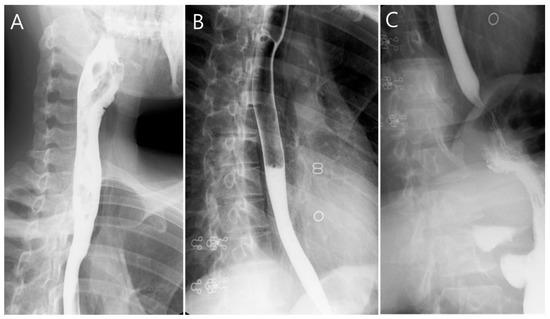

2. Case Presentation